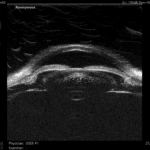

ABSolu od Quantel Medical je nový A/B/S/UBM systém ponúkajúci intuitívny softvér, ktorý urýchľuje prácu a vyhodnocovanie snímok.

ABSolu prichádza s novým typom 20 Mhz B-sondy, pozostávajúcej z piatich snímačov rôznych priemerov, ktorá zvyšuje hĺbku poľa o 70% a laterálne rozlíšenie o 27%. To umožňuje simultánne vyšetriť patológie sklovca, sietnice a orbity bez ústupkov na kvalite snímky. Štandardizovaná sonda zas zabezpečuje diagnostiku tumorov, odlúpenia sietnice, či Gravesovej choroby. Sondy B15 a B20 obsahujú senzor, ktorý automaticky zisťuje a v reálnom čase znázorňuje polohu sondy a smer lúča.

- väčšia hĺbka ostrosti umožňujúca vizualizáciu celého oka,

- vynikajúce rozlíšenie od prednej časti sklovca až k stenu,

- zobrazovacia technológia UBM s rôznymi zobrazovacími režimami,